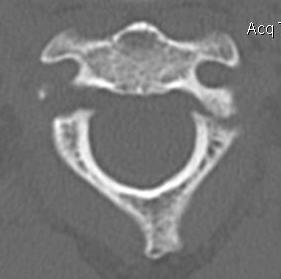

Bilateral pars fracture of C2

Traumatic spondylolisthesis of C2

CT scan